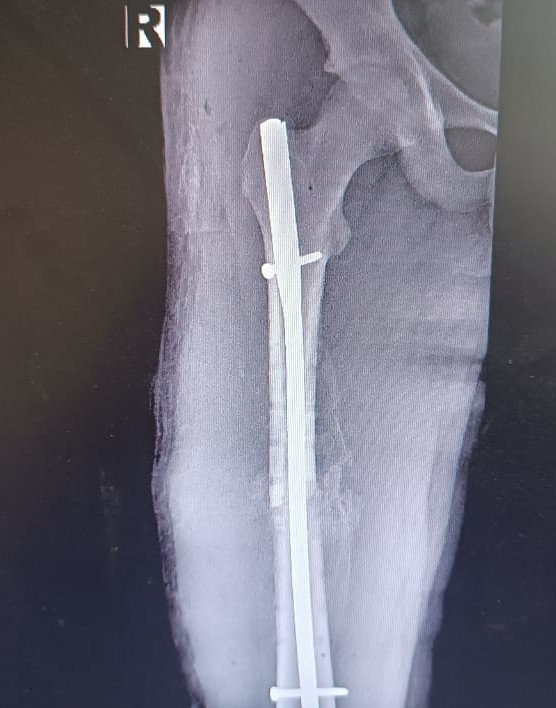

В хирургическом отделении Муромской детской районной больницы внедрено лечение переломов трубчатых костей у детей. Благодаря полученной лицензии на оказание высокотехнологичной медицинской помощи муромские врачи теперь могут проводить операции инновационным методом – блокирующим интрамедуллярным остеосинтезом (БИОС). А применение современного оборудования – электронно-оптического усиления изображения (С-дуга) – позволяет проводить операции с максимальной точностью и без рисков для здоровья.

Уже 18 сентября 2025 года врачи – Косимов Ойбек Толибович и Смирнов Максим Андреевич – успешно провели такую операцию ребёнку с переломом бедра, полученным в результате ДТП (столкновение мотоцикла с легковым автомобилем).